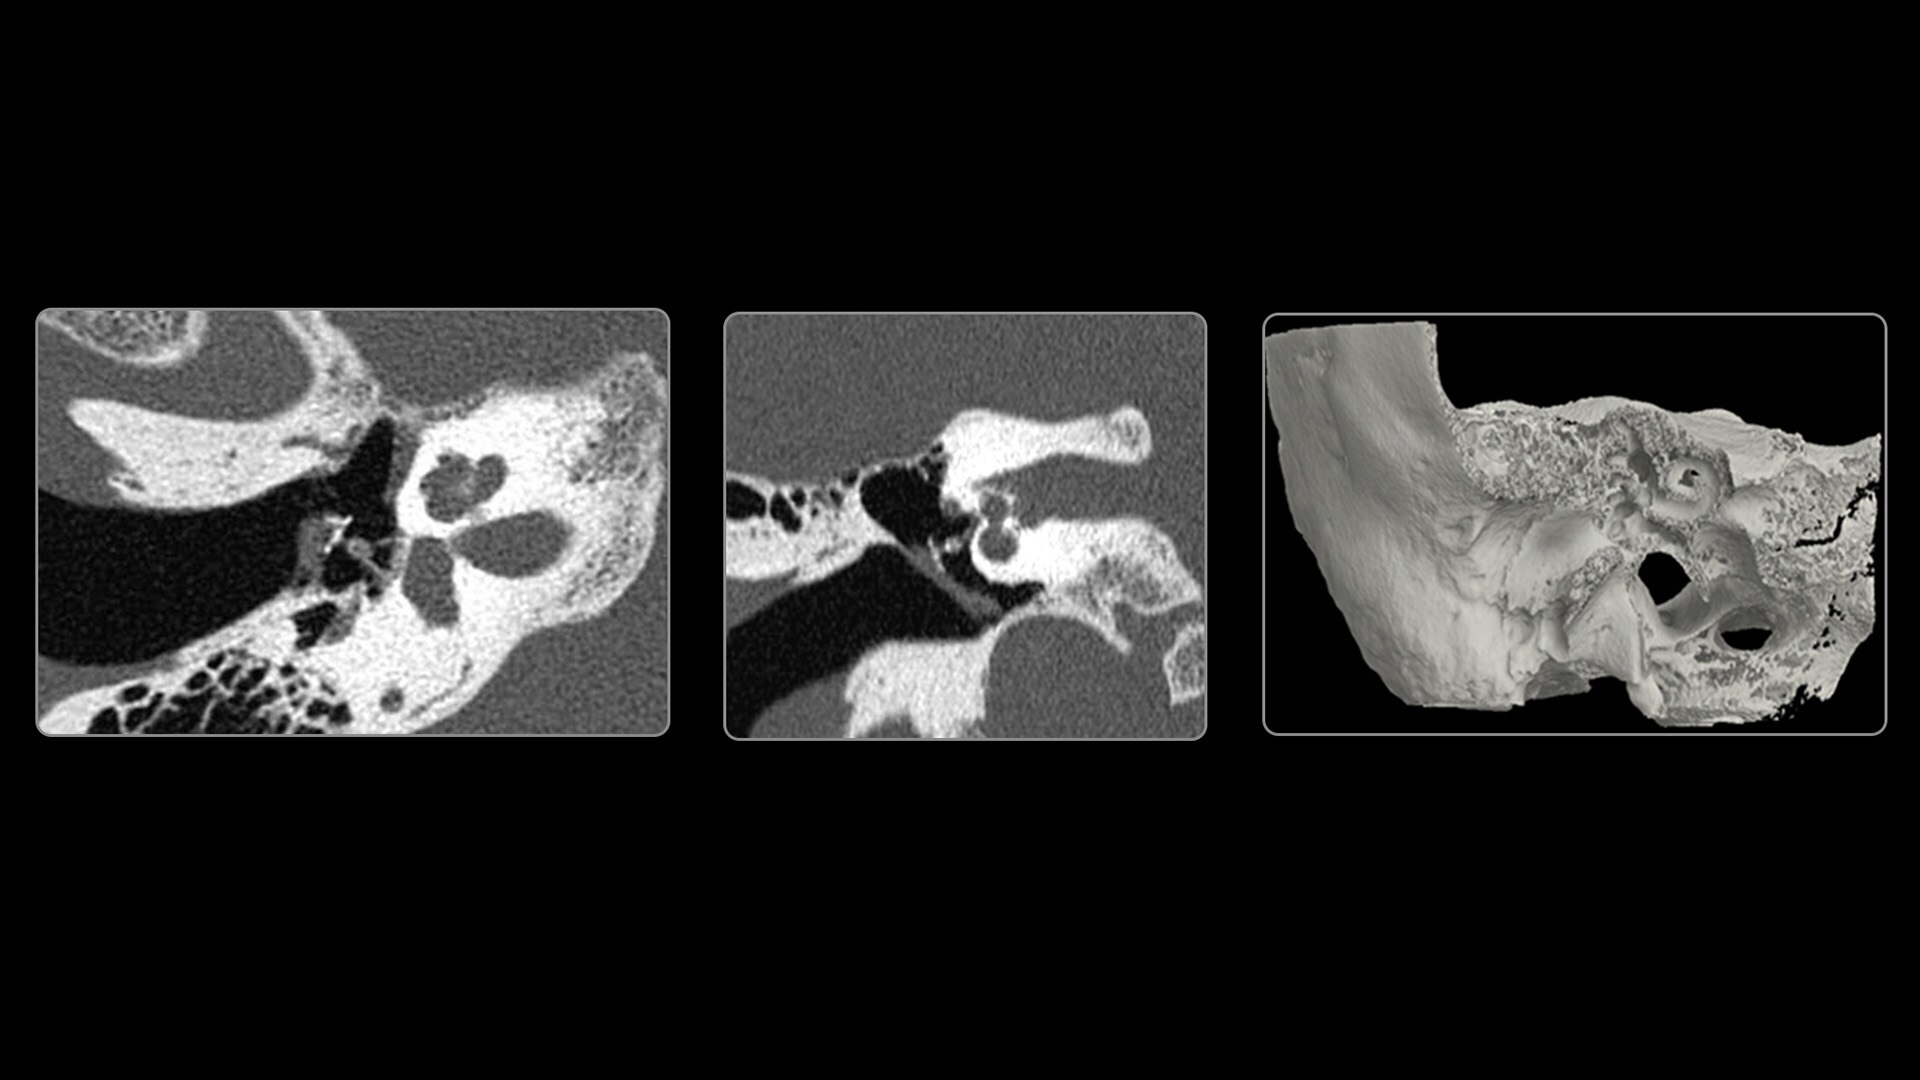

With ultra-high spatial resolution scanning capability, Photonova Spectra is designed to help you see incredibly fine details, such as coronary plaque delineation, small microvascular vessels and even tiny structures of the inner ear.

Experience our industry-leading 8 cm detector coverage, combined with up to 0.23 sec rotation speed and ultra-high sampling rates featuring a 50 cm field of view (FOV) in all scan modes. This enables wide-coverage ultra-high definition imaging with reduced organ movement for exceptional image clarity.